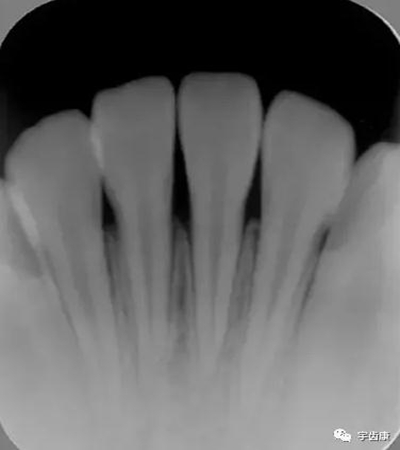

X線閱片知識(shí)

牙體解剖知識(shí)

牙體各個(gè)面的解剖厚度